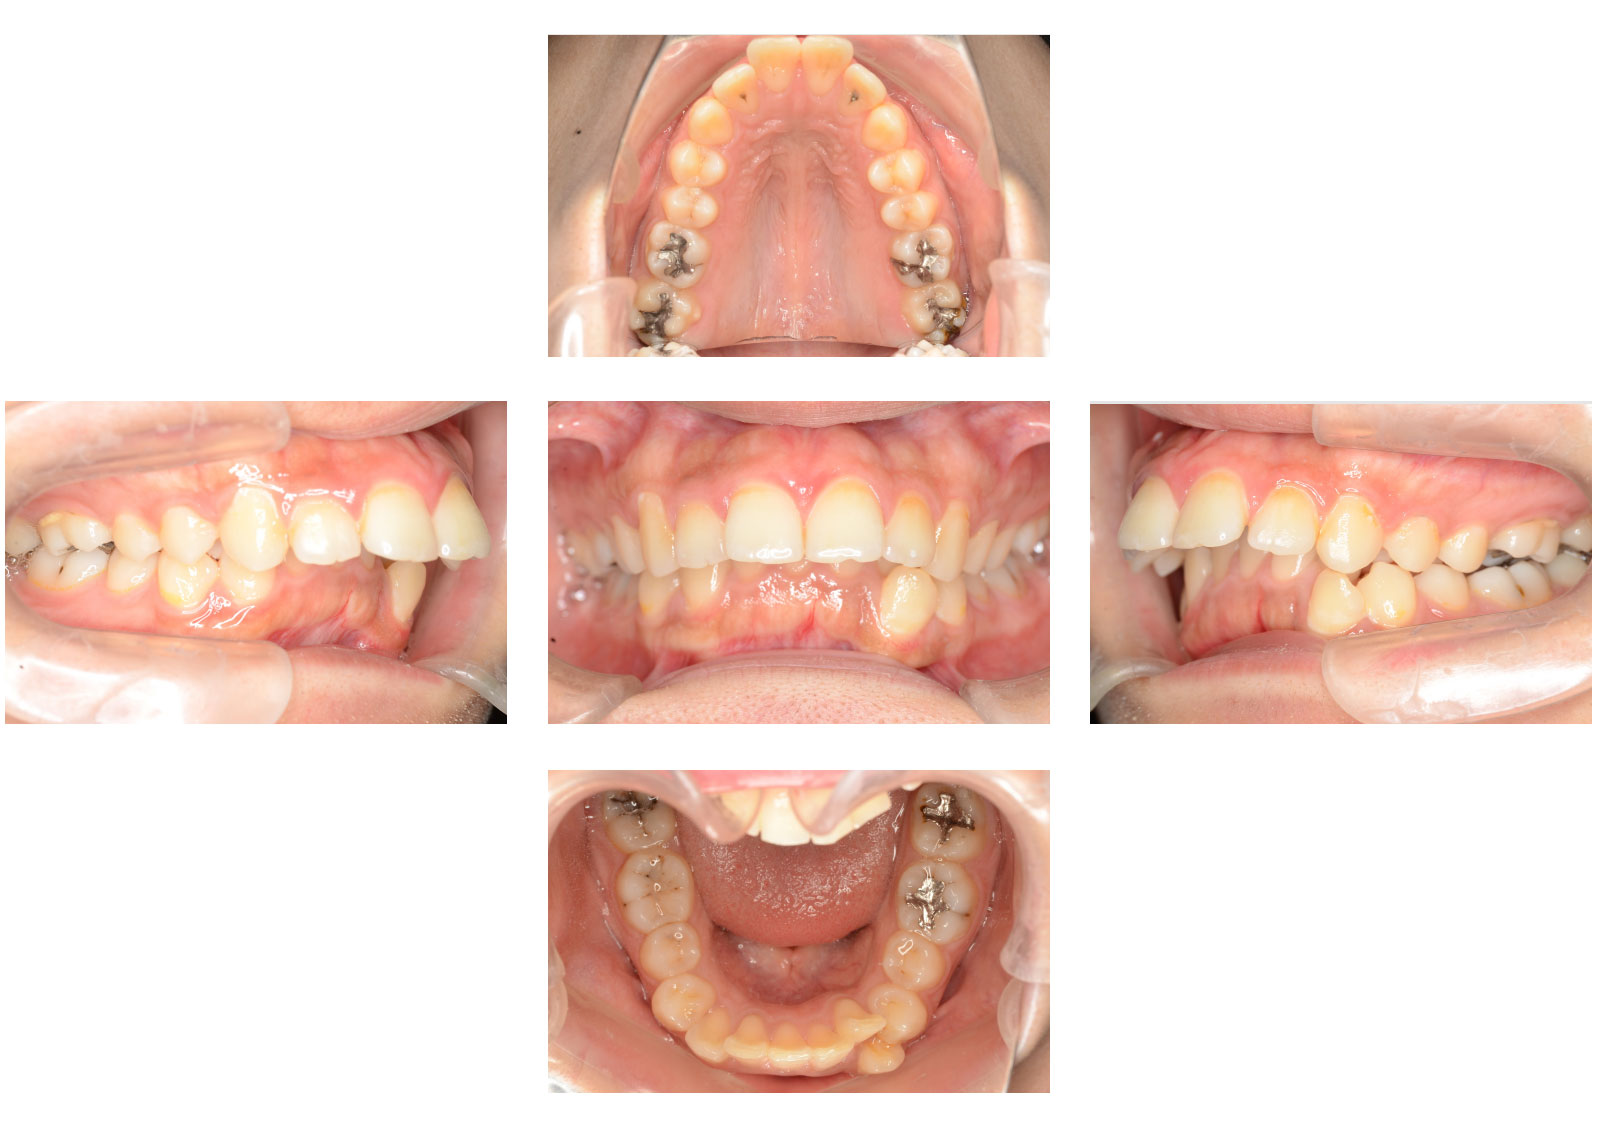

矯正前

症例画像